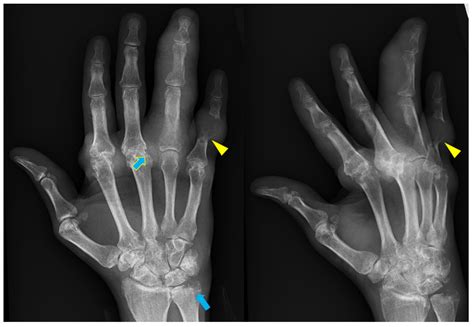

• Fractures: Identifying any breaks or cracks in the bones.

• Fractures: These can be simple, compound, or comminuted, depending on the severity.

• Bone Development Issues: Such as delayed growth or abnormal bone shapes.

• Congenital Anomalies: Conditions like syndactyly (fused fingers) or polydactyly (extra fingers).

• Infections: Signs of bone infections or osteomyelitis.